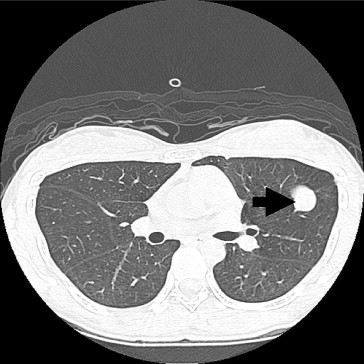

Abdominal ultrasonography at 39 weeks gestation showed a hypoechoic tumor, 33 mm in size over the right lobe of the liver. A male infant weighing 3.396 kg was delivered by Cesarean section due to dysfunctional labor, which was performed at gestational week 41. One week later, computed tomography showed a lobulated hypervascular mass about 47 mm in S7 of the liver (Fig. 2). Wedge resection of S7 was carried out one month after delivery with an uneventful recovery.

Computed tomography showed a hypervascular mass, 47mm in size, over segment 7 of ...

Figure 2.

Computed tomography showed a hypervascular mass, 47 mm in size, over segment 7 of the liver (arrow).